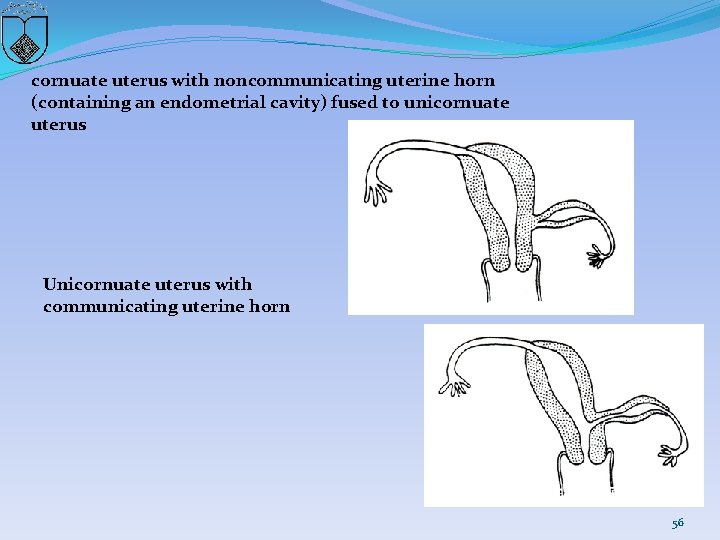

cornuate uterus with noncommunicating uterine horn (containing an endometrial cavity) fused to unicornuate uterus Unicornuate uterus with communicating uterine horn 56